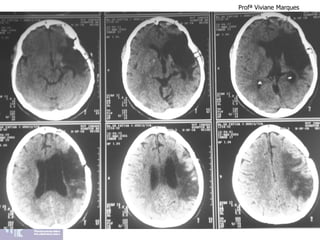

Afasia de Wernicke

LESÃO NO GIRO TEMPORAL SUPERIOR – ÁREA 22 DE WERNICKE

Afasia de Broca

LESÃO NO GIRO FRONTAL INFERIOR PARTE OPERCULAR – ÁREA 44 DE BROCA

Afasia de Wernicke ProfªViviane Marques LESÃO NO GIRO TEMPORAL SUPERIOR – ÁREA 22 DE WERNICKE

Afasia de Broca ProfªViviane Marques LESÃO NO GIRO FRONTAL INFERIOR PARTE OPERCULAR – ÁREA 44 DE BROCA